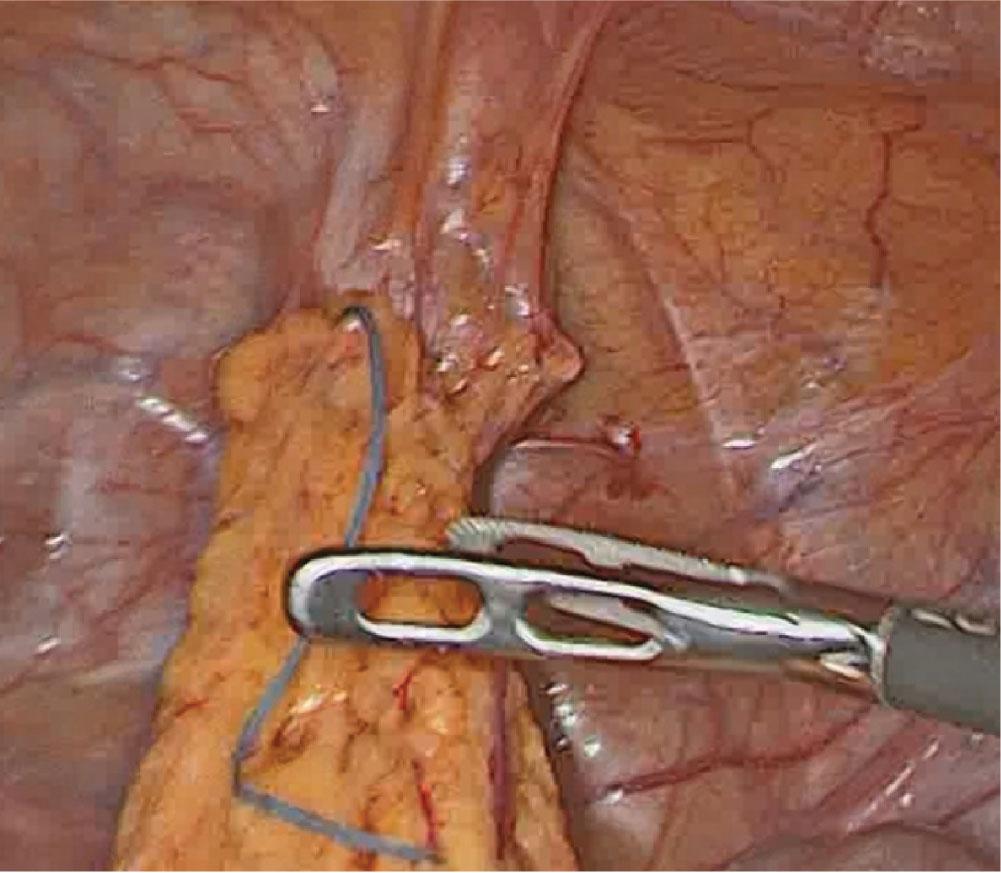

At laparoscopy, the contraceptive device was found to be fully covered by omental adhesions and adherent to the urinary bladder’s dome and superior surface.

Atraumatic laparoscopic freeing of the IUD from omental and urinary bladder adhesions.

At surgery, the uterus was found to be intact (no visible evidence of perforation). The IUD turned out to be localized intraperitoneally, adherent to the urinary bladder dome and its superior surface by omental adhesions (Fig. 2). This location was in line with the findings from the computed tomography. A step-by-step atraumatic laparoscopic freeing of the device from the omental and urinary bladder adhesions enabled its final removal (Fig. 3). No blood loss was observed. The patient was discharged on the second postoperative day in a good general condition.